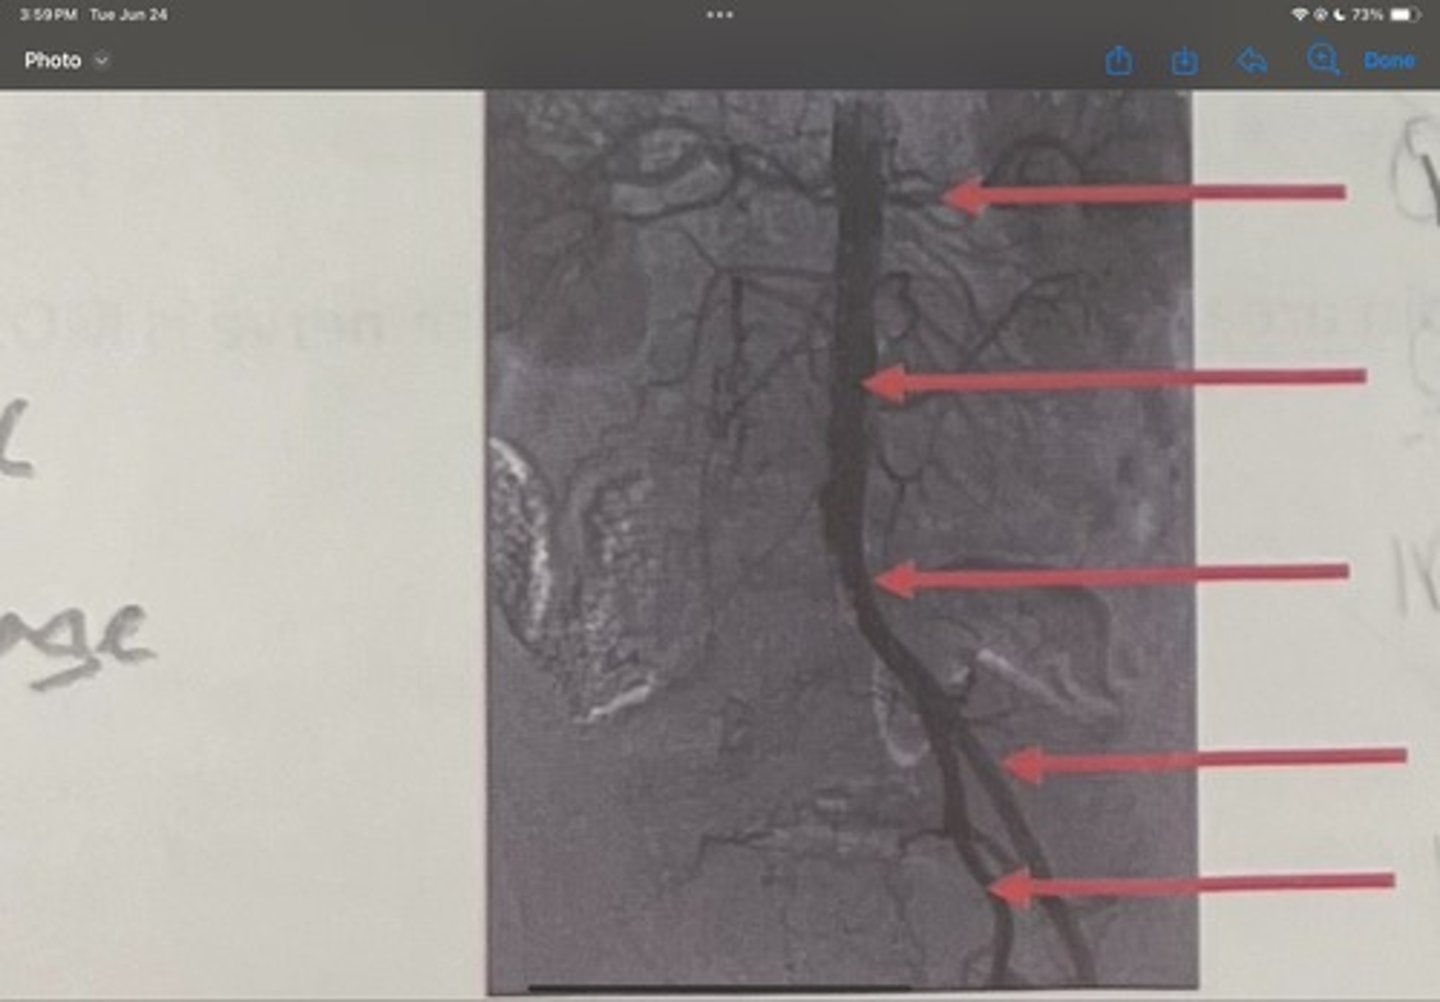

Renal artery

What is the 1st one

Abdominal aorta

What is the 2nd one

Common iliac artery

What is the 3rd one

External iliac artery

What is the 4th one

Internal iliac artery

What is the 5th one

right common iliac artery blockage

What is the pathology of the image